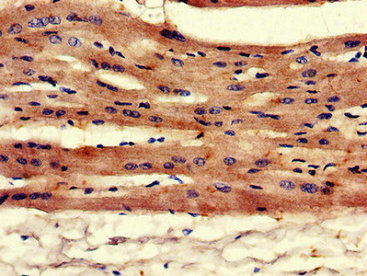

圖片:

應(yīng)用范圍:ELISA, IHC, IF

Application Recommended Dilution IHC 1:20-1:200 IF 1:50-1:200 -